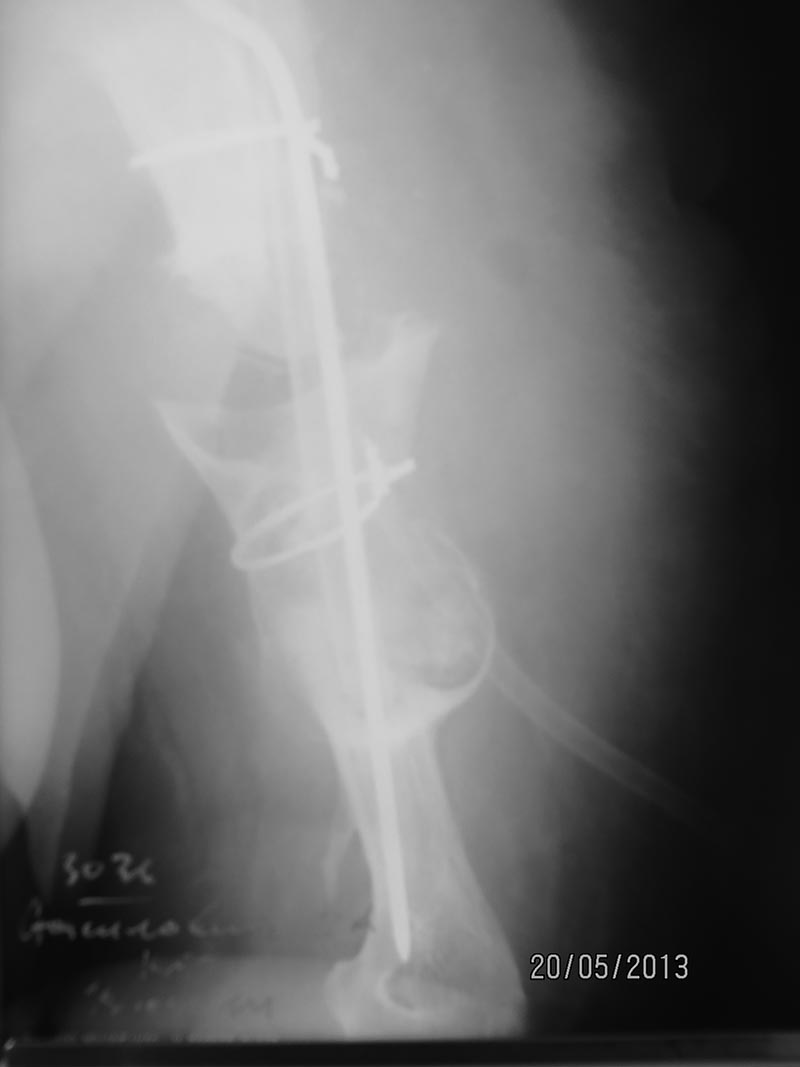

В итоге: выполнить остеосинтез пластиной не реально, винты в склерозированной скорлупе держаться отказывались. Произведена кортикальная костная пластика трансплантатом из малоберцовой кости + гвоздь Богданова и проволочный серкляж. Рентгенограмма мягкая, но видно.